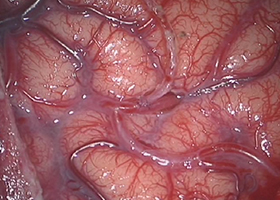

実際の手術

-

浅側頭動脈と脳表の血管 -

頭皮と脳表血管の吻合 -

術中蛍光撮影でバイパス血流の確認 -

脳表を筋肉で覆う。